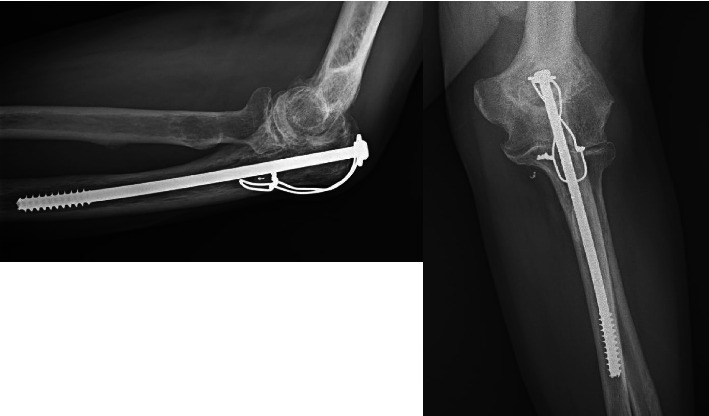

Abstract Image